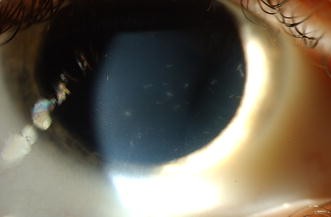

Acute Conjunctivitis And Corneal Foreign Bodies Secondary To Tarantula Hairs Cmaj